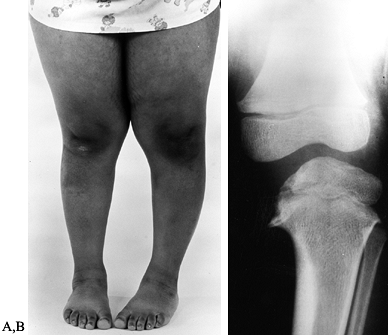

Figure 169.7. A:

Clinical photograph of a 5-year-old African-American girl with left infantile tibia vara. Observe the obesity, the unilateral left genu varum deformity, and the associated medial tibial torsion. B: Standing radiograph of the left knee demonstrates Langenskiöld grade III changes in the medial aspect of the proximal tibial epiphysis and metaphysis. Notice the metaphyseal beaking. |